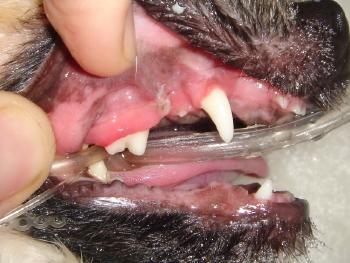

治療終了後の写真です。